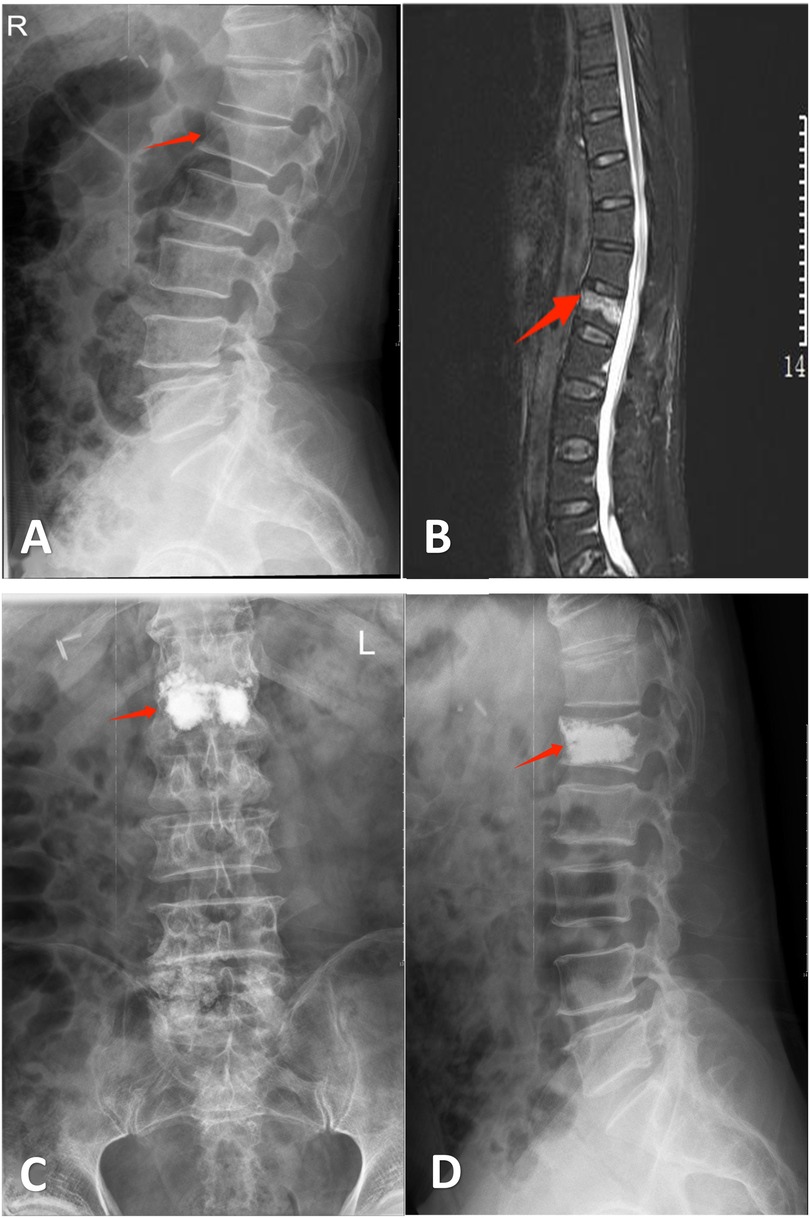

For DSP group patients, a definitive diagnosis was established during outpatient evaluation with the completion of all preoperative imaging and laboratory tests. One-day admission was arranged for surgical intervention on the day of hospitalization. TIP group patients underwent preoperative workup after hospital admission. Both cohorts underwent PKP procedures under local anesthesia with monitored anesthesia care (MAC), following standardized surgical protocols (14) (Figures 1, 2).

Figure 1. Mr. Hu, a 74-year-old male, was admitted to our hospital due to “low back pain for 1 day following trauma”. Diagnosis: L1 vertebral compression fracture. He underwent bilateral percutaneous kyphoplasty (PKP). Persistent postoperative pain on day 1 precluded same-day discharge, necessitating transfer to the conventional treatment group. (A) Lateral radiograph demonstrating wedging deformity of the L1 vertebral body. (B) Sagittal MRI revealing an L1 vertebral fracture. (C,D) Postoperative anteroposterior and lateral radiographs after bilateral PKP at L1.